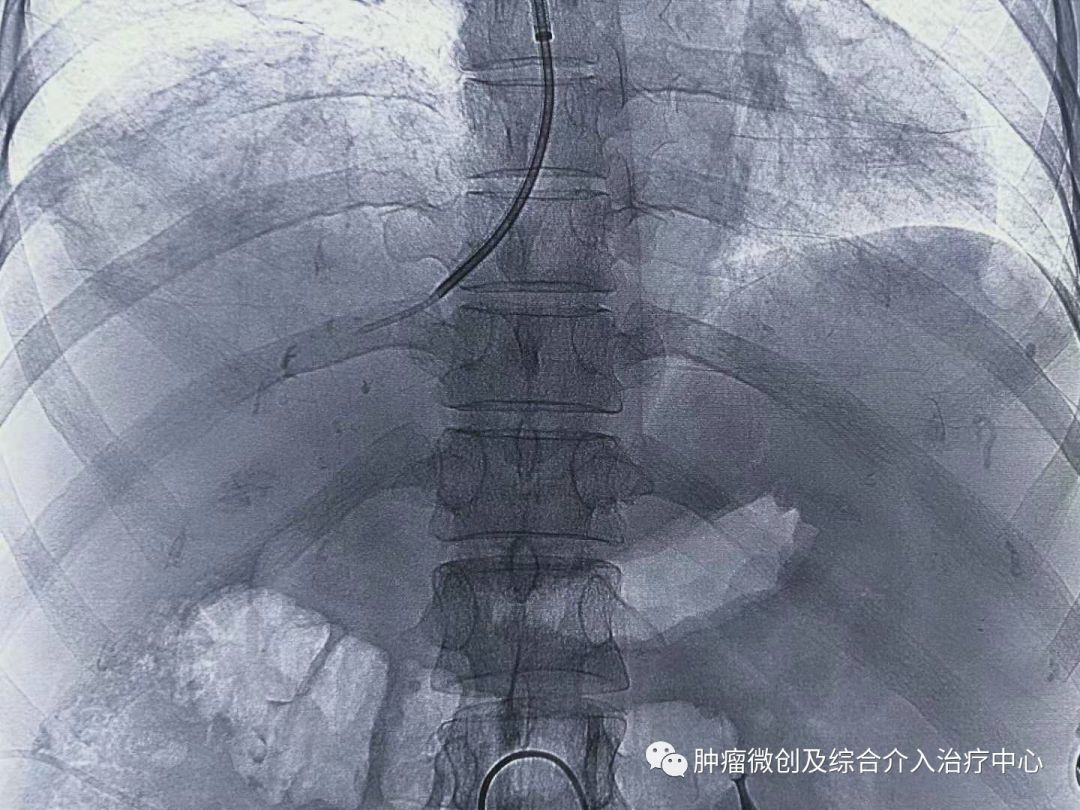

手术过程:

术前定位穿刺部位: